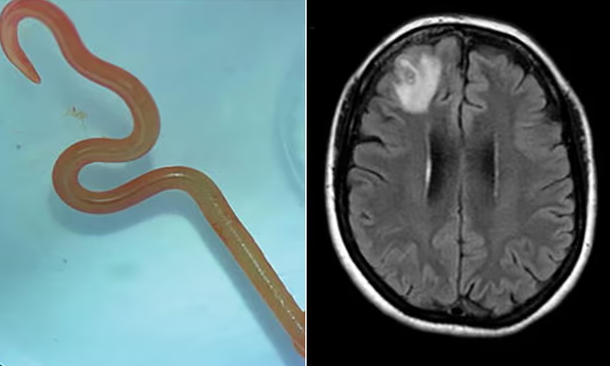

報導指出,這條8公分活體蛔蟲寄生在婦人的大腦裡,之後醫師從婦人受損的腦額葉中取出這條蟲蟲,而且蟲蟲被取出時還是活跳跳狀態,醫師也研判,蟲蟲寄生在婦女腦內已達2個月。傳染病科醫師賽納納亞克(Sanjaya Senanayake)就形容:「當醫師用鑷子夾起這個物體時,手術室裡的每個人都震驚無比,因為發現這是一條蠕動的、活的8公分紅色蠕蟲。」

據悉寄生在婦人腦內的蛔蟲名叫「Ophidascaris robertsi」,這種蛔蟲通常寄生在澳洲常見的地毯蟒蛇體內。澳洲寄生蟲專家侯賽因(Mehrab Hossain)在《新發傳染病》(Emerging Infectious Diseases)期刊上就指出,他懷疑這名婦人可能吃下被蟒蛇糞便和寄生蟲卵汙染的植物,之後成為「意外宿主」。